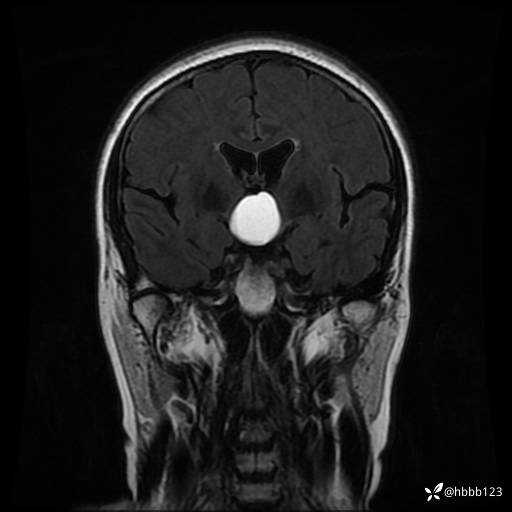

T2 Flair冠状位重建:

T1WI 增强 冠状位重建: